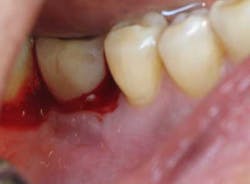

Fig. 2: Clinical probing showing suppuration around the implant-supported crown.